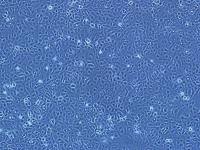

- 生长状态:

贴壁生长

1590(人乳腺癌细胞)复苏

文献和实验移植动物模型肿瘤生长及转移速度较快,可用来评价乳腺癌发生发展及转移过程中免疫应答的作用。异种移植一般采用人源组织或细胞接种于免疫缺陷小鼠(如重度免疫缺陷鼠 NCG),能模拟人恶性肿瘤成瘤后过程,可用于基础和临床研究。但人乳腺癌存在不同的分子分型,且人乳腺癌细胞系相对于其他癌种成瘤难度更大,且不稳定,因此选择合适的细胞系也十分重要。针对乳腺癌不同的分子分型,集萃药康细胞资源库配备丰富的乳腺癌细胞株以及热门靶点人源化改造的细胞资源,用于构建乳腺癌移植瘤模型。 表 1. 部分集萃药康乳腺癌细胞资源展示